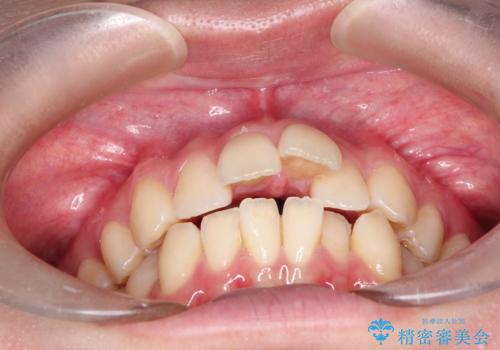

ワイヤーによる抜歯矯正でガタガタの改善

- 前歯のがたがたを主訴に来院されました。

上下の前歯が前方に傾斜しているのもあり、内側に前歯をひっこめるために上下左右の歯を1本ずつ抜歯して矯正することとしました。

ガタガタも改善しましたが、前歯が内側に引っ込むことにより口元もすっきりして、唇が閉じやすくなりました。